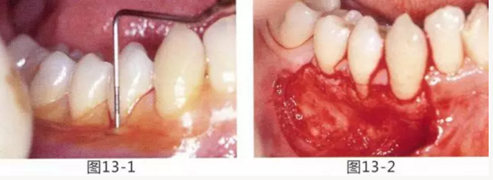

圖13-1 使用碘溶液進行染色,頰側基本看不到角化牙齦,且無口腔前庭的狀態(tài)。

圖13-2 為了擴張口腔前庭,獲取附著齦而進行了游離齦移植術。受皮床一定不能發(fā)生移動,盡可能使厚度均等。

圖13-3 手術剛結束的狀態(tài)。通過骨膜縫合的褥式縫合將移植片固定,使其無法移動。

圖13-4 手術完成2年后的狀態(tài)??谇磺巴サ玫綌U張,即使正在進行正畸治療,也沒有妨礙到清潔。